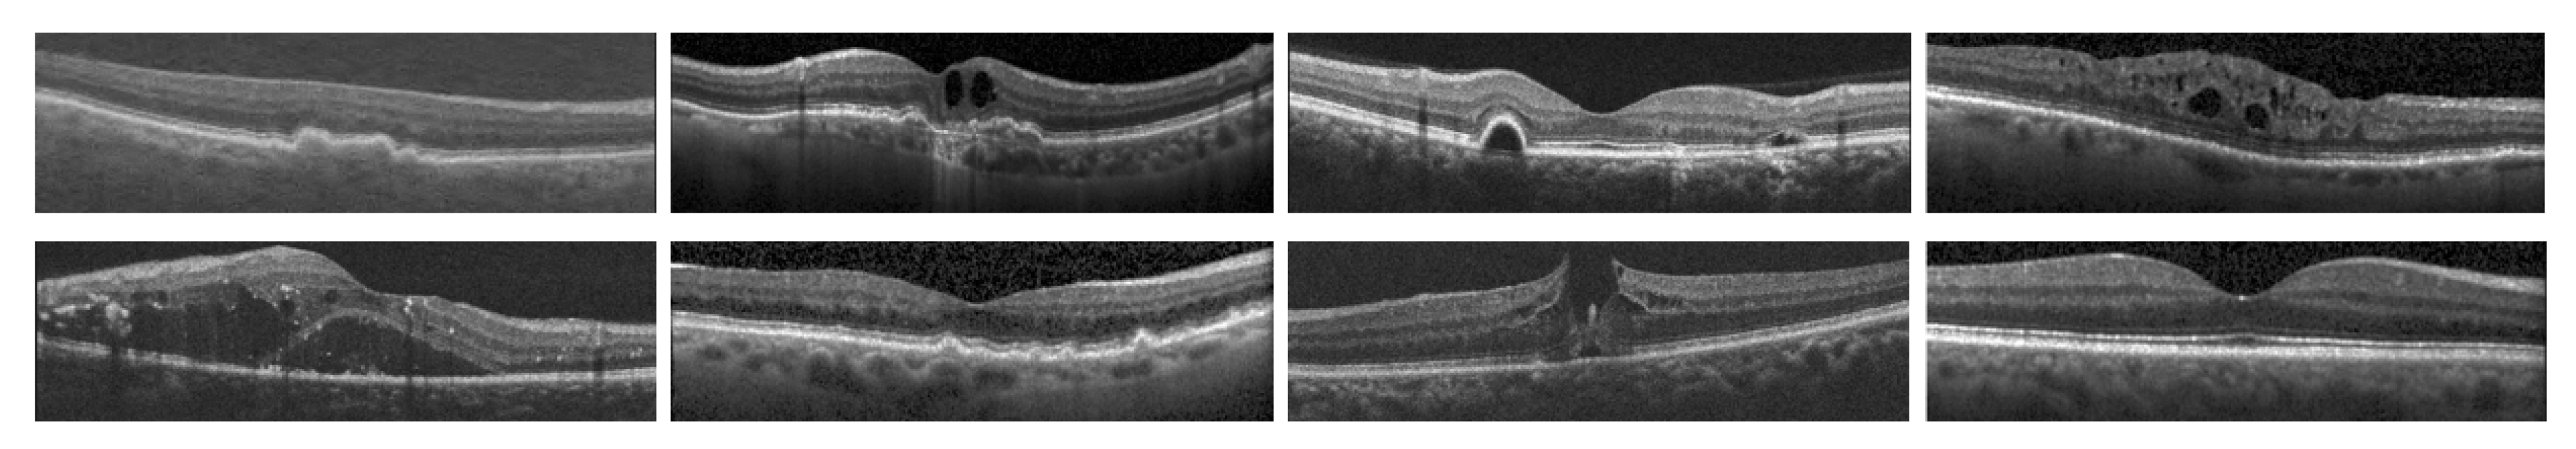

2. Review of OCT Datasets for Ocular Disorder Classification